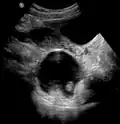

A small (4 cm) dermoid cyst of an ovary, discovered during a C-section

Ovaries normally grow cyst-like structures called follicles each month. Once an egg is released from its follicle during ovulation, follicles typically deflate. Sometimes fluid accumulates inside the follicle, forming a simple (containing only fluid) cyst.[2] The majority of these functional cysts resolve spontaneously.

While all ovarian cysts can range in size from very small to quite large, dermoid cysts are not classified as functional cysts. Dermoid cysts originate from pluripotent germ cells (which are present at birth) that differentiate abnormally, developing characteristics of mature dermal cells. Complications exist, such as torsion (twisting), rupture, and infection, although their incidence is rare. Dermoid ovarian cysts which are larger present complications which might require removal by either laparoscopy or laparotomy (traditional surgery).[3][4] Rarely, a dermoid cyst can develop in the vagina.[5][6][7]